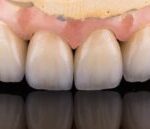

Vorher: Alte Implantat-Krone kleinerer Schneidezahn ; nicht ansprechende Ästhetik Frontzähne

Nachher